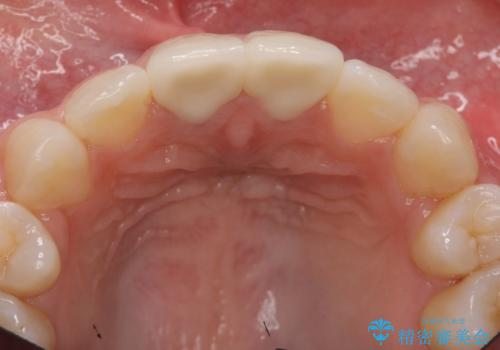

- 神経のない前歯が変色していたため、矯正治療後にセラミックで修復しました。

セラミックの前に、全体をオフィスホワイトニング(エクセレント)して周りの歯を白くして色をなじませました。

- 38万円(上顎両側1:ジルコニアクラウン スタンダード 10万円x2、ファイバーコア 2万円x2、 精密根管治療(再治療)9万円x1、仮歯 1万円x2)、ホワイトニング(エクセレント)3万円費用は治療当時の料金となります

神経をとった前歯は変色してきますので、セラミックで被せた方が良いです。

また、神経が無い歯は虫歯になっても自覚症状が出ないため、劣化するプラスチックで継ぎはぎするのは変色も防げないですし、オススメしません。歯が薄くなっており、破折のリスクがあるため、クラウンをおすすめします。